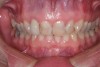

Figure 7  The canine teeth were moved mesially into the space left by the congenitally missing lateral incisors.

Figure 7

Figure 8  Having the premolars in the position of the canine leaves inadequate contour to provide disclusion of the posterior teeth. Note how the incisal plane moves apically after passing the lateral position.

Figure 8

The origin of the patient’s esthetic concerns and functional issues proved to be the same: the patient was congenitally missing her lateral incisors. The solution for this esthetic deficit during her adolescent years was to move the canines into the position of the lateral incisors and then recontour (flatten the incisal edge) to make it look like a lateral. The premolars were then moved mesially into the canine position (Figure 7). The end result was a solution that closed an edentulous space, yet left a functional deficit. The premolars lacked the proper contour to allow immediate posterior disclusion in an excursive movement (Figure 8). After many years, this functional deficit led to the previously described signs of instability.